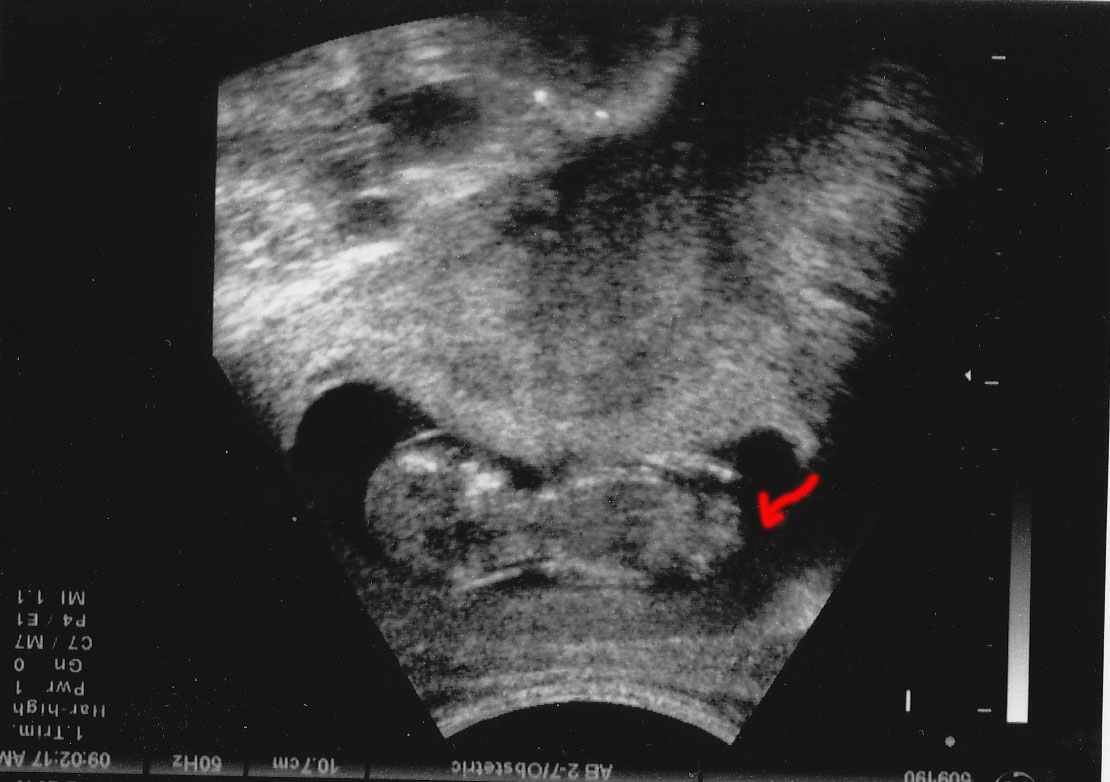

Well I had my 12 week scan today and ALL the pictures given to me were head on of the baby's face. Then I was just looking at them and I noticed this one. Not even sure if this a the profile of the baby, and I flipped it too. Well let me know what you think.